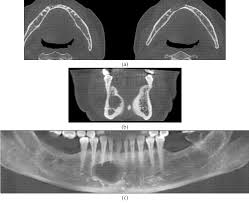

1-Computerized Tomography (CT) :

-         Technique: The patient is usually scanned in the axial plane

sections taken in succession by a beam ; the desired image appears when these sections combined on computer . the sectioned imagies ranges from 64 to 128.

Advantages:

Ø In this technique, due to the sectioning of tissues,

organs are not superposed on each other , so it helps in assessment of normal growth pattern and detecting of : craniofacial deformaties

Ø Orofacial trauma and fractures

Ø TMJ ankylosis or fractures

Ø Differences in airway volumes after rapid palatal expansion , examination of the maxillary sinus.

Disadvantages:

Ø Expensive,

Ø very high dose of radiation

Ø Not available in every hospital

Ø In addition, CT data is insufficient compared

with other soft-tissue imaging techniques.

2-Cone Beam Computerized Tomography (CBCT) :

-          technique : Craniofacial CBCT devices are designed to overcome some of the limitations of conventional CT scanning devices.

-         There are a lot of differences among the CBCT devices including patient positioning, scan time, resolution, radiation dose, and clinical ease of use of crosssectional area.

• Ø it allows 3D(volumetric) data with very low

• Ø CBCT allows re-alignment of 2-dimensional

• Ø Determination of normal and abnormal craniofacial anatomy,

• Ø Determination of 3D maxillo-mandibular relationship during facial growth.

Ø The main factor of weakness in image quality is

image artifacts , The actual color of the skin and soft tissue images cannot be determined